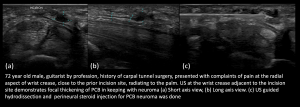

- Post Carpal Tunnel Release (CTR) surgery, Palmar Cutaneous Branch (PCB) neuroma and Flexor Carpi Radialis (FCR) tenosynovitis

Fig 14: POST CTR SURGERY PALMAR CUTANEOUS BRANCH (PCB) NEUROMA AND FCR TENOSYNOVITIS PCB neuroma and PCB hydrodissection with steroid injection

Fig 15: POST CTR SURGERY PALMAR CUTANEOUS BRANCH (PCB) NEUROMA AND FCR TENOSYNOVITIS Normal Median Nerve at Carpal tunnel; Persistent PCB neuroma

Fig 16: POST CTR SURGERY PALMAR CUTANEOUS BRANCH (PCB) NEUROMA AND FCR TENOSYNOVITIS FCR tenosynovitis with tendinopathy - Post Open Reduction Internal Fixation (ORIF)/Carpal Tunnel Release (CTR), median nerve neuroma/thickening at the wrist crease proximal to the carpal tunnel